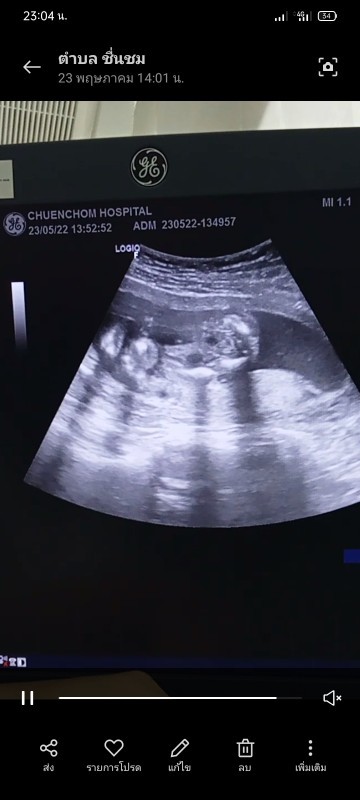

ช่วยดูหน่อยค่ะแบบนี้ชายหรือหญิง

บ้านนี้ชอบโชว์จู๋คะ 23w หนัก700กรัม